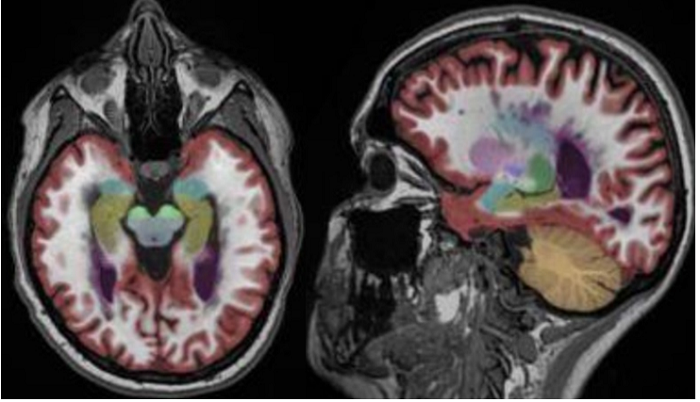

医生诊断用的MRI图像

在现在的医疗机构,医生获取患者的MRI图像后,往往是根据经验判断患者的大脑是否萎缩。因为用经验判断的东西差异化很大,所以漏诊的现象时常出现。

脑医生系统标注的图像

如上图所示,红色的区域是大脑皮层灰质,这个区域的萎缩是阿尔兹海默症患者重要的早期诊断指标。脑医生系统通过自动标注受试者大脑重要结构的体积与正常指标作对比就可以对受试者情况作出判断